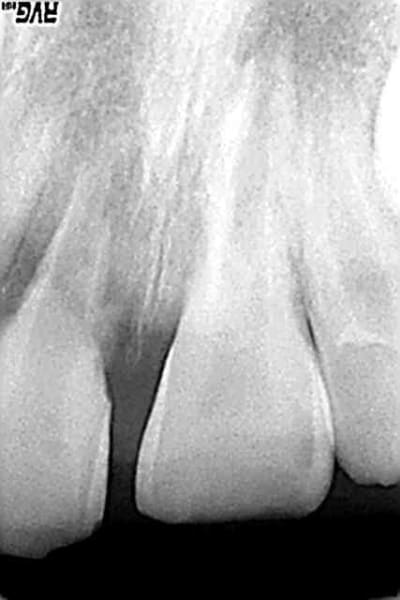

ankylose et rhizalyse,les osteoblastes et les osteoclastes qui travaillent dur!

et cela va continuer

d'apres les stats,a cet age la,la resorption radiculaire est terminee en deux ans,la couronne tombera toute seule

ton patient aura 10 ans

et toujours pas de 14!

l'agenesie asymetrique pourrait te faire envisager une acrobatique autotransplantation de la 24 (avant la resorption totale de la 11 et la fermeture apicale de la 24)

les deux autres solutions etant :

-bagues sur les 6 et arc avec 11 en attente d'implant(mais 8 ans de maintenance!!)

-traitement odf pour fermer l'espace,la aussi pas tres excitant, avec l'agenesie de la 14,on est deja en manque de "matiere"

bref,tu gardes,bichonnes la 11 et previens bien les parents et l'enfant!